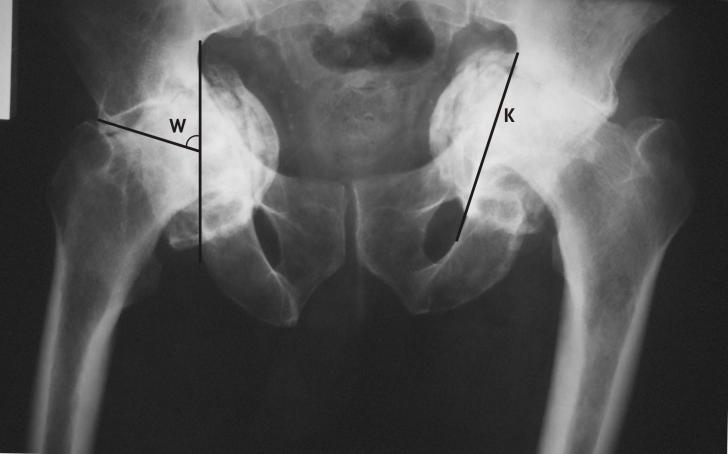

Protruzie acetabulara cu coxartroza bilaterala - prezentare de caz

PROTRUZIE ACETABULARA CU COXARTROZA BILATERALA - PREZENTARE DE CAZ PRIMARY TOTAL HIP ARTHROPLASTY IN BILATERAL ACETABULAR PROTRUSION (Abstract): Acetabular protrusion is a clinical entity consisting of deepening of the acetabulum and cCiteste tot ... 2493 cuvinte